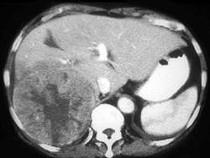

男,69岁,肝区疼痛,消瘦乏力三月余,CT检查如图,请作出最可能诊断()A.肝囊肿B.肝脓肿C.肝血管瘤D.肝转移瘤E.巨块型肝癌

问题 男,69岁,肝区疼痛,消瘦乏力三月余,CT检查如图,请作出最可能诊断()

选项 A.肝囊肿 B.肝脓肿 C.肝血管瘤 D.肝转移瘤 E.巨块型肝癌

答案 E